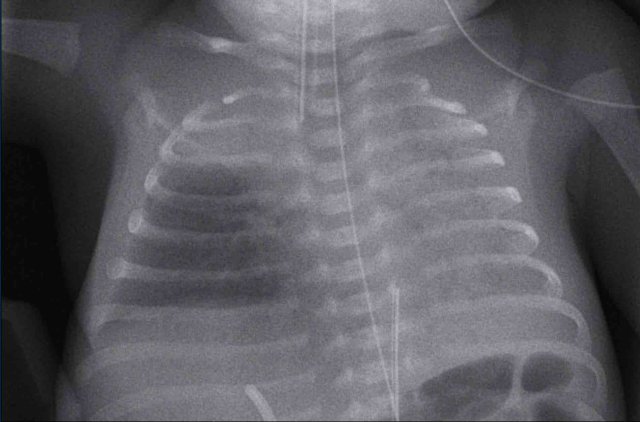

29 weeks + 1, day one. CPAP.

Findings:

• Reticulogranular opacification of lungs

• Air bronchogram

• Consolidation in the right lower lobe

• Heart, vessels and diaphragm are poorly defined.

• Malposition of umbilical vein catheter (arrow), probably in a pulmonary vein.

• Nasogastric tube (NG tube) in good position.

This is a severe case of RDS.

The differential diagnosis includes pulmonary infection due to the asymmetric consolidation.